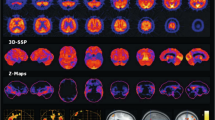

A Structure of [18F]PF-06684511. B Averaged 32–180 min SUVs for [18F]PF-06684511 at baseline and under heterologous blocking with 5 mg/kg LY2886721 (PO, 2 h prior to PET scanning). CB cerebellum, ACC anterior cingulate cortex, FC frontal cortex, TC temporal cortex, CAU caudate, PUT putamen, THA thalamus, OC occipital cortex, PC parietal cortex, AMY amygdala, HIP hippocampus. Adapted with permission from Zhang, L. et al. Identification of a novel positron emission tomography (PET) ligand for imaging β-site amyloid precursor protein cleaving enzyme 1 (BACE1) in brain. J. Med. Chem. 61(8), 3296–3308 (2018). Copyright 2018 American Chemical Society. C Representative summed [18F]PF-06684511 PET images (0–123 min) for test-retest scans in healthy volunteers. Adapted with permission from Arakawa, R. et al. PET imaging of beta-secretase 1 in the human brain: radiation dosimetry, quantification, and test-retest examination of [18F]PF-06684511. Eur. J. Nucl. Med. Mol. Imaging 47, 2429–2439 (2020). D Structure of [11C]RO6807936. E In vitro autoradiographical distribution of [3H]RO6807936 binding (1 nM) in rat brain, as well as baboon and human hippocampal sections. Neuronal staining with cresyl violet in human hippocampal tissue is also shown. DG dentate gyrus. Adapted with permission from Honer, M. et al. RO6807936 as a novel positron emission tomography (PET) radiotracer for in vitro and in vivo visualization and quantification of beta-site amyloid precursor protein cleaving enzyme (BACE1) in the rodent and baboon brain. J. Label. Compd. Radiopharm. 66, 222–236 (2023).

Researchers at Pfizer were the first to report PET imaging of BACE1 with [18F]PF-06684511 (Fig. 2A)32. In whole-cell assays, PF-06684511 displayed IC50<1 nM and was 15 times more selective for BACE1 over BACE2. Time-activity curves from NHP imaging with [18F]PF-06684511 were not initially reported, but a subsequent quantitation study with this tracer revealed relatively slow kinetics, with a peak whole-brain uptake of 2.2 SUV at 20 min, which was halved to 1.0 SUV by 120 min33. Heterologous blocking with 5 mg/kg LY2886721 (intravenously, 2 h pre-scan) reduced the 32–180 min averaged [18F]PF-06684511 uptake by 48–80% in NHPs, depending on the brain region (Fig. 2B). The radiotracer was advanced to healthy human volunteers34. A 2TCM fits both the NHP and human PET data well, although the authors suggest that Logan's graphical analysis may be a suitable alternative33,34. No reference regions can be used when imaging this target because BACE1 is ubiquitously expressed throughout the brain. Unfortunately, the measured test-retest variability in healthy human volunteers was determined to be ~16% (Fig. 2C), so a >20% change in VT is necessary to measure significant BACE1 inhibition34. The high test-retest variability, paired with the slow washout kinetics, are limiting factors in the use of [18F]PF-06684511 for clinical research. Nonetheless, [18F]PF-06684511 remains the most advanced PET radiotracer for imaging BACE1 to date.